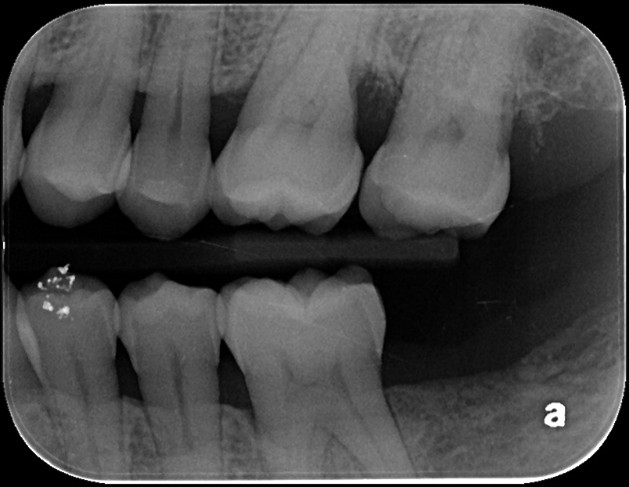

臨床檢查與影像判讀

- 牙周囊袋深度:左上第一大臼齒遠心側探測深度達 8mm,屬於重度牙周病

- 牙齦狀態:探測有出血現象,顯示局部發炎反應仍明顯

- X 光影像判讀:顯示該顆牙齒遠心側出現垂直性齒槽骨缺損,牙根周圍的齒槽骨高度明顯下降

治療前影像